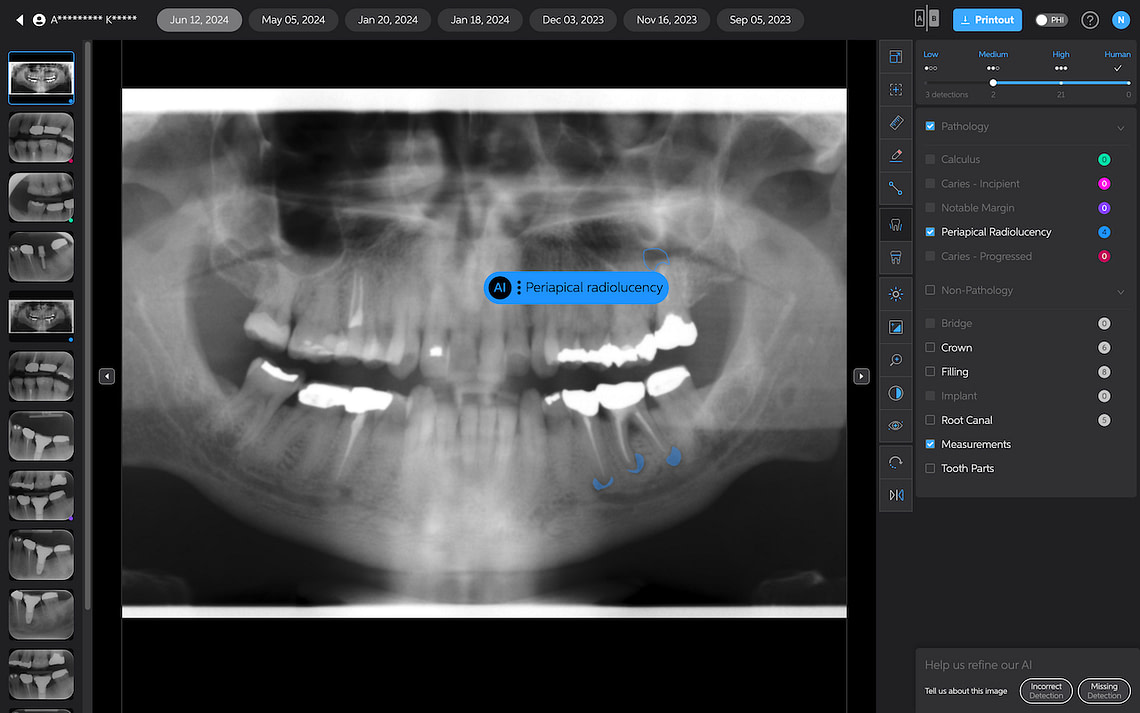

Periapical Radiolucencies

These are self-explanatory. They are outlined in blue on periapical radiographs. While this could help draw attention to potential issues, interpreting these findings would still rely heavily on the dentist's expertise.